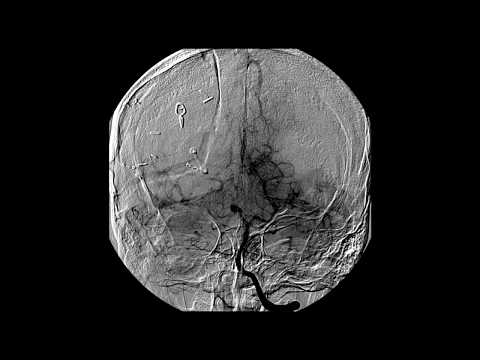

Hellow guys, Welcome to my website, and you are watching Microsurgical Resection of a Paramedian Parietal Arteriovenous Malformation. and this vIdeo is uploaded by Barrow Neurological Institute at 2021-01-19T14:26:10-08:00. We are pramote this video only for entertainment and educational perpose only. So, I hop you like our website.